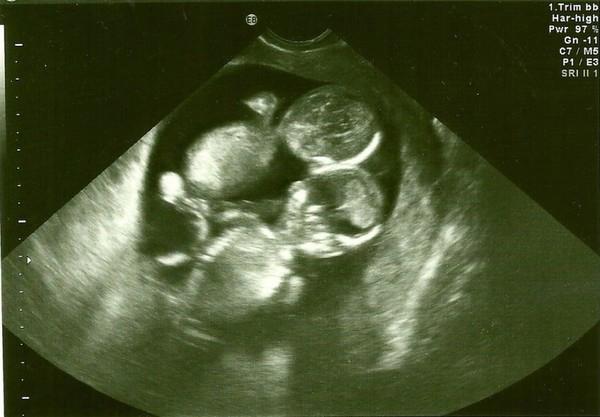

Hai vợ chồng cô đã nhận 2 đứa con nuôi nhưng Kate vẫn luôn nuôi hy vọng tự mình mang thai, sinh con. Và rồi một ngày, Kate bỗng cơ thể có những dấu hiệu mang thai nên vội vàng đến bệnh viện kiểm tra. Và cả hai vợ chồng đã vỡ òa khi bác sĩ siêu âm xác nhận đúng là Kate đang mang thai. Thậm chí hạnh phúc dường như được nhân đôi khi bác sĩ ra hiệu có 2 tim thai.

Sở dĩ bác sĩ làm vậy là vì ông lo lắng cơ hội sống sót của hai bé là quá thấp. Nếu chia sẻ tin tức sớm sẽ khiến mọi người phải thất vọng. Hai bé trong bụng Kate bị mắc hội chứng Monoamniotic. Đây là hội chứng xảy ra khi hai bào thai chia sẻ chung một túi ối không màng ngăn khiến dây rốn quấn quanh thai nhi trong quá trình phát triển. Điều này dễ dẫn đến tình trạng thai thiếu oxy và chết lưu trong bụng mẹ. Xác xuất xảy ra hội chứng Monoamniotic này là 1% và tỷ lệ sống sót chỉ đạt 50%.